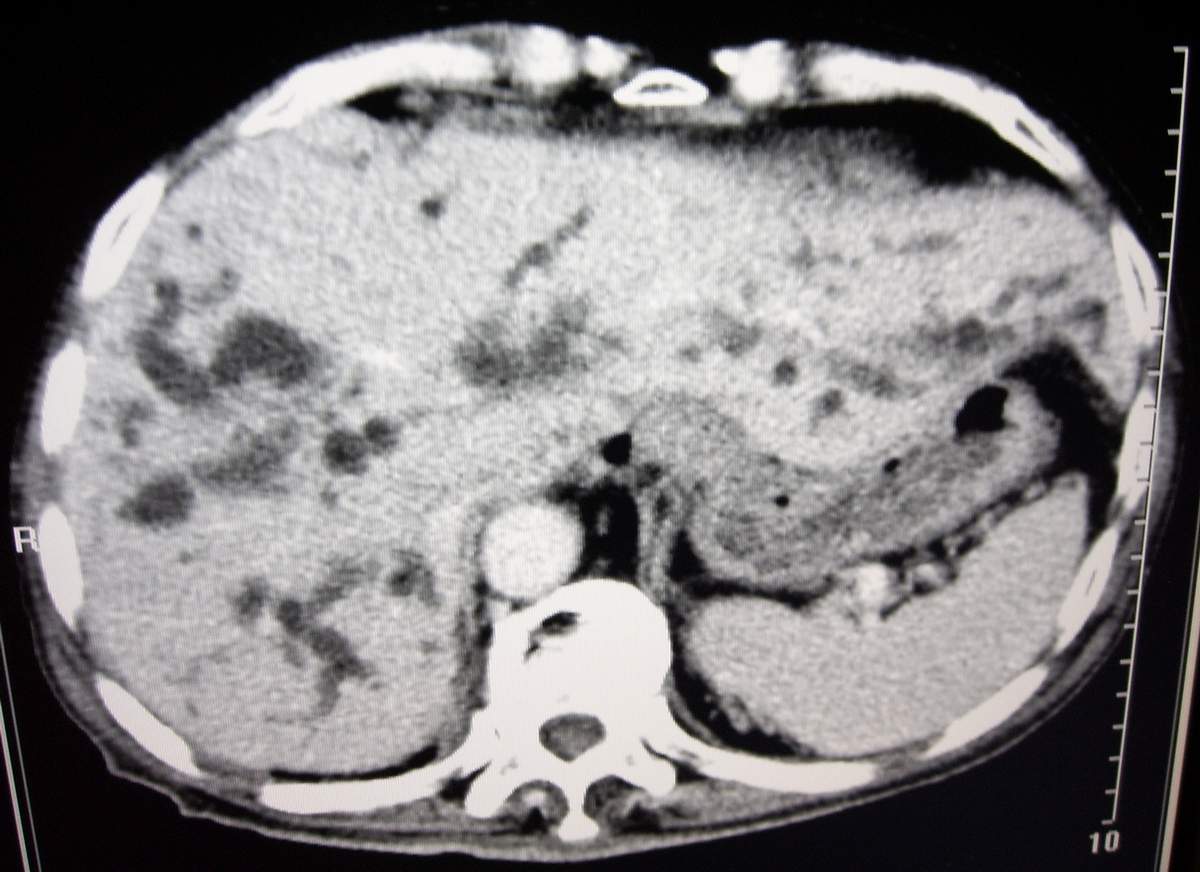

男,77岁,病史不详。

考虑:1、华枝睾吸虫肝病(肝外胆管未见扩张,肝内胆管不成比例扩张,也就是失去分支规律的扩张,呈

外部呈柱状或囊状扩张,中部无明显扩张,而且边界不清);

肝内胆管普遍扩张,呈串珠状改变,走行不规则,且右叶胆管周围肝实质密度呈条片状减低,未见占位性病变,外周胆管及胰管扩张不及肝内胆管.胰腺钩突形态正常,胰十二指肠区域未见明显结节及肿块,初步考虑慢性胆管炎可能性大.请结合临床病史.另外用宽窗看一下吉氏筋膜有无增厚.

肝内胆管普遍扩张,呈串珠状改变,走行不规则,且右叶胆管周围肝实质密度呈条片状减低,未见占位性病变,外周胆管及胰管扩张不及肝内胆管.胰腺钩突形态正常,胰十二指肠区域未见明显结节及肿块,初步考虑慢性胆管炎可能性大.请结合临床病史.另外还有、胆囊炎、胆囊结石,左肾囊肿。

支持!当然,肝门区胆管细胞癌不能排除。期待随访结果。